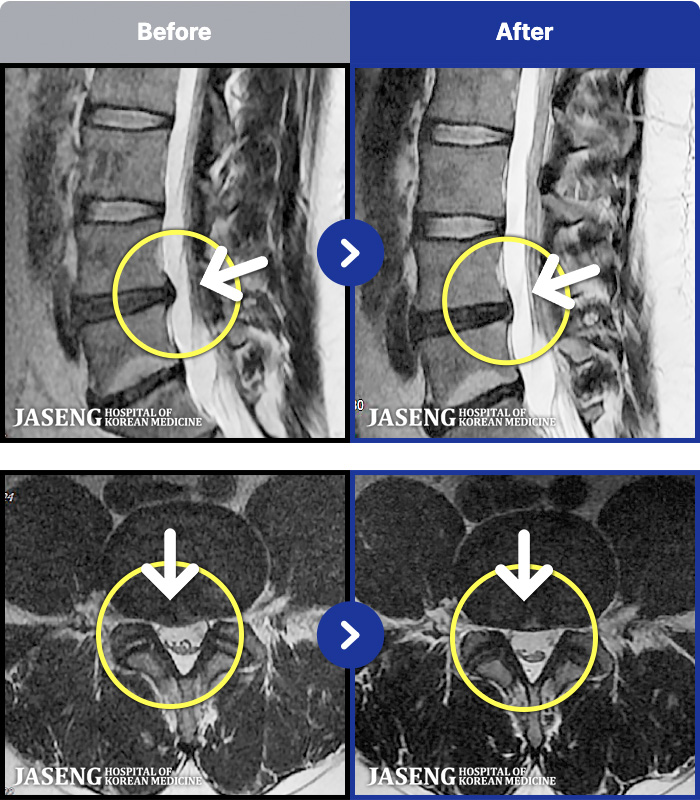

54 MRI ũ ʸ Ȯϼ.